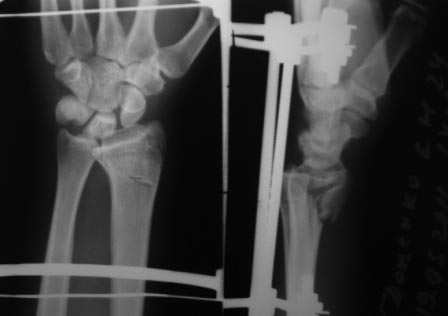

Остается как самый уместный способ - чрескостный остеосинтез с применением аппарата внешней фиксации: т.к. он весьма бюджетный и позволяет достичь необходимой репозиции.

Вариант чрескостного остеосинтеза обдумывался.

Но при повторной репозиции с экстензией кисти к тылу было отмечено недостаточное смыкание отломков суставной фасетки луча.

Учитывая,что при ЧКДО репозиция и удержание отломков происходит за счет лигаментотаксиса, мне более надежным показался вариант накостного остеосинтеза.

P.S (дистрактор на предплечье накладывать случалось- особенно удобно при застарелых переломах с деформацией )

Согласен с последним предложением относительно применения аппарата внешней фиксации. Повреждения луча по типу "переднего Бартона" очень хорошо закрыто устраняеются в АВФ, при этом завершающим элементом (после достижения репозиции посредством постепенной дистракции) может быть введение спицы с упором (конечно, вне проекции срединного нерва и сухожилий сгибателей пальцев)и обеспечение боковой компрессии переднего отломка к основному фрагменту.

АВФ очень разнообразны, мы (отделеие хирургии кисти ГКБ 4 г. Москвы) используем только две полудуги и две штанги смонтированные на двух спицах Киршнера, проведенных через кости предплечья и основания 2-5 пясьных костей (аппарат Лазарева-Коршунова), дополнительных спиц не проводим.